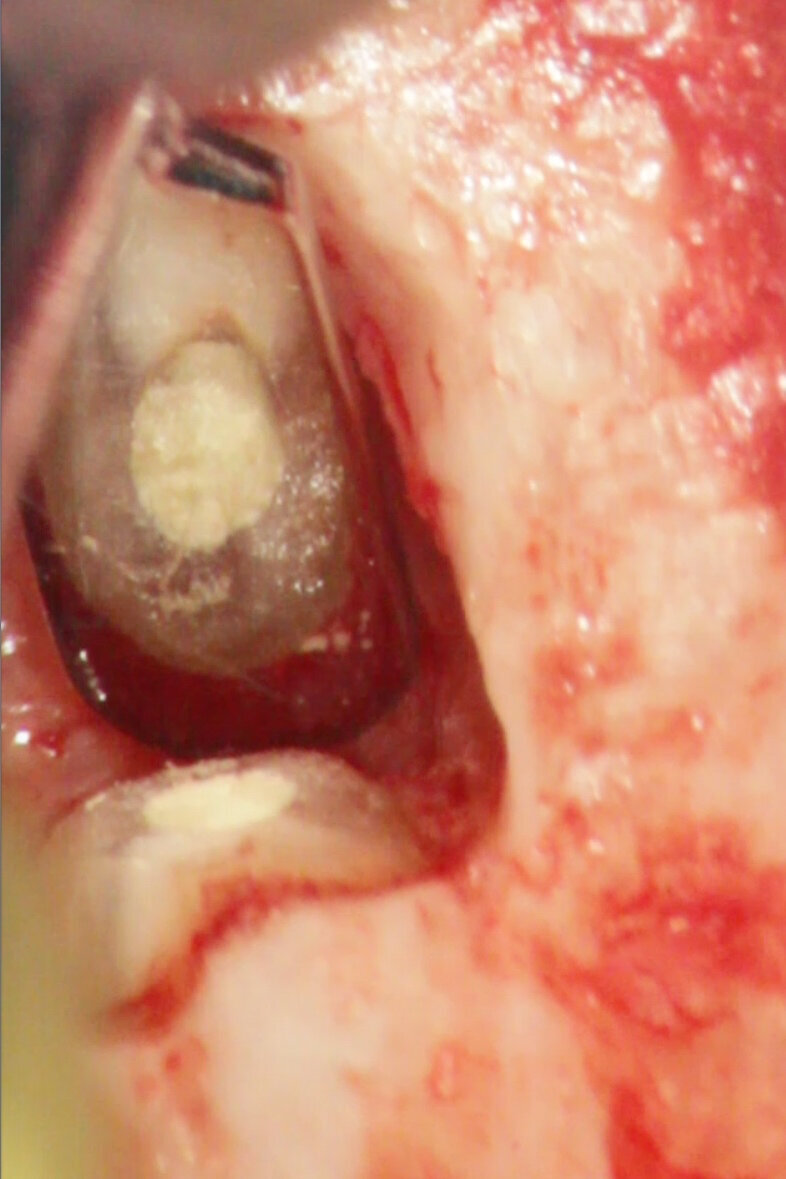

Chirurgia apicale

MTA è il materiale che vanta i migliori risultati come materiale da otturazione per la chirurgia apicale. L’MTA è stato associato ad una minore infiammazione, a formazione di nuovo cemento e alla rigenerazione del tessuto periradicolare (Torabinejad e Chivian 1999) (Figg. 4a-4f).